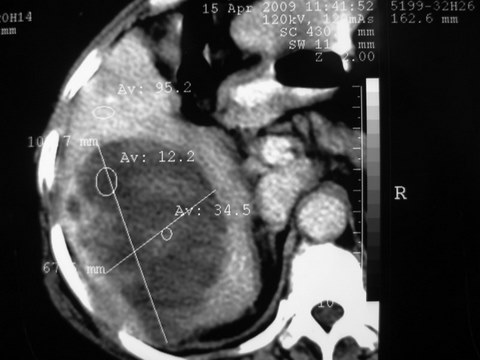

患者 女 51岁 两天前感觉上腹疼,无明显诱因,b超示肝右叶囊实性占位,边缘清楚,其内回声不均匀,ct增强如图,大家看看是什么 ,病人一年前及两月前b超检查只是提示胆囊炎

外院术后,证实肝癌合并出血

特点:1,病灶发展迅速,(2月前正常)[br] 2,囊实性,且并边界清晰光滑,呈右后叶赘生性。囊性区无强化,实性部分较多轻度强化,边界欠清。考虑囊腺癌或囊腺瘤。

出病理 中分化肝细胞癌合并出血

感谢楼主反馈病理结果(中分化肝细胞癌合并出血)。好病例,学习了!